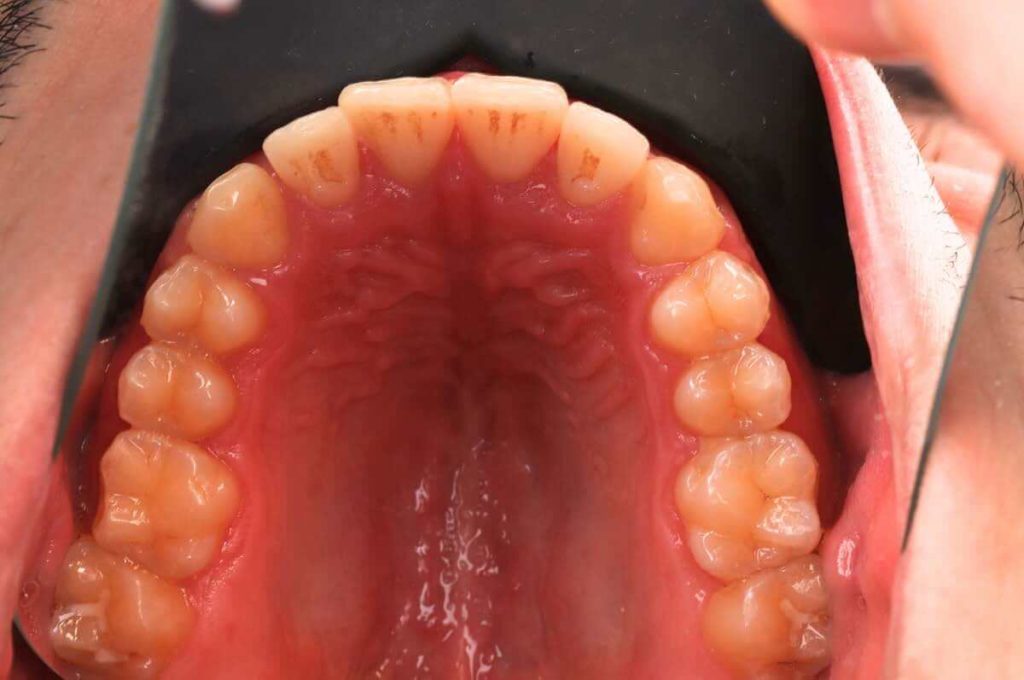

SITUACIÓN INICIAL

CLASE I MORDIDA CRUZADA EN LATERALES

• Clase I con mordida cruzada en los incisivos laterales.

• Apiñamiento moderado en el arco superior e inferior.

• Desplazamiento de la línea media superior.

• Arco normal con necesidad de expansión.